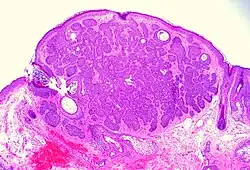

Nodular basal-cell carcinoma (also known as "classic basal-cell carcinoma") accounts for 50% of all BCC.[29] It most commonly occurs on the sun-exposed areas of the head and neck.[30]: 748 [31]: 646 Histopathology shows aggregates of basaloid cells with well-defined borders, showing a peripheral palisading of cells and one or more typical clefts.[29] Such clefts are caused by shrinkage of mucin during tissue fixation and staining.[32] Central necrosis with eosinophilic, granular features may also be present, as well as mucin. The heavy aggregates of mucin determine a cystic structure. Calcification may also be present, especially in long-standing lesions.[29] Mitotic activity is usually not so evident, but a high mitotic rate may be present in more aggressive lesions.[29] Adenoidal BCC can be classified as a variant of NBCC, characterized by basaloid cells with a reticulated configuration extending into the dermis.[29]